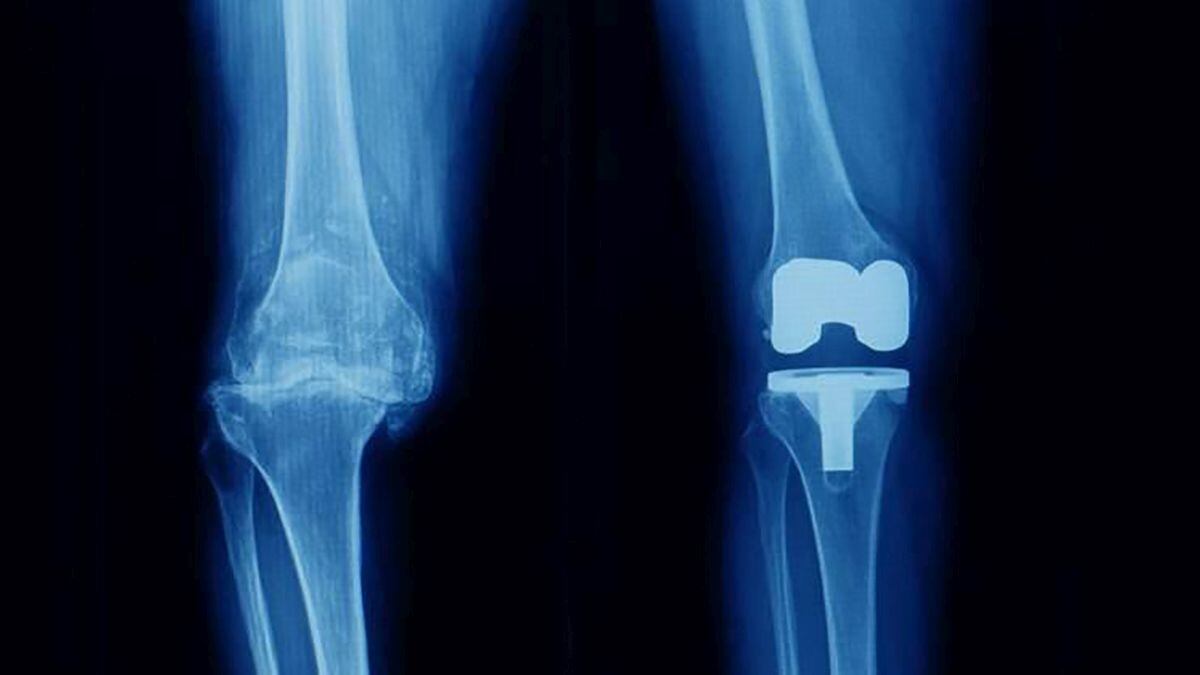

Prótesis de rodilla

La Gerencia de Asistencia Sanitaria de Soria (GASSO) ha publicado en la Plataforma de Contratación del Sector Público la adjudicación de 21 procedimientos quirúrgicos de traumatología (sustitución de cadera y sustitución de rodilla con prótesis) a pacientes con derecho a prestación sanitaria pública en el Área de Salud de Soria, por un importe de 87.750 euros, al Hospital Recoletas de Burgos. El plazo de ejecución del contrato desde su formalización es de un mes

Este nuevo proceso es complementario de un expediente del mismo servicio y prestación ejecutado este año. En julio, la Gerencia de Asistencia Sanitaria de Soria adjudicó la concertación externa de 41 procesos de sustitución total de rodilla y 20 de cadera al Hospital Moncloa Grupo HLA S.A.U., de Madrid, por un importe estimativo de 266.000 euros.

El objetivo es conseguir la mejora y estabilización de las listas de espera, y para ello se necesita la concertación externa de procedimientos quirúrgicos, mediante la contratación de entidades, empresas o profesionales ajenos al sistema público de Salud de Castilla y León. Con ello se pretende complementar la actividad realizada en el propio Hospital Santa Bárbara y conseguir reducir las demoras de estas dos especialidades, que entre ambas suponen el 56% del total de la lista de espera quirúrgica.